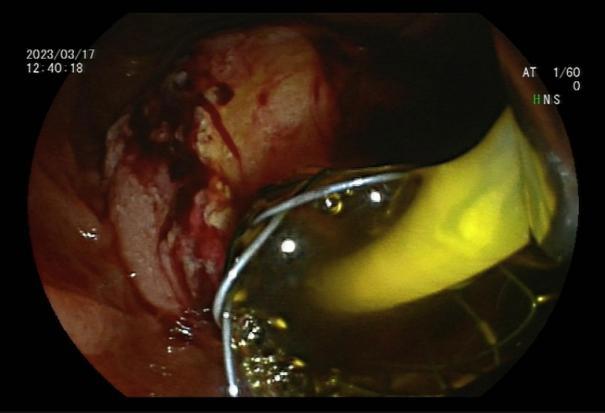

直肠巨大绒毛状腺瘤 内镜下粘膜剥离过程

粘膜剥离术后创面 剥离的巨大腺瘤